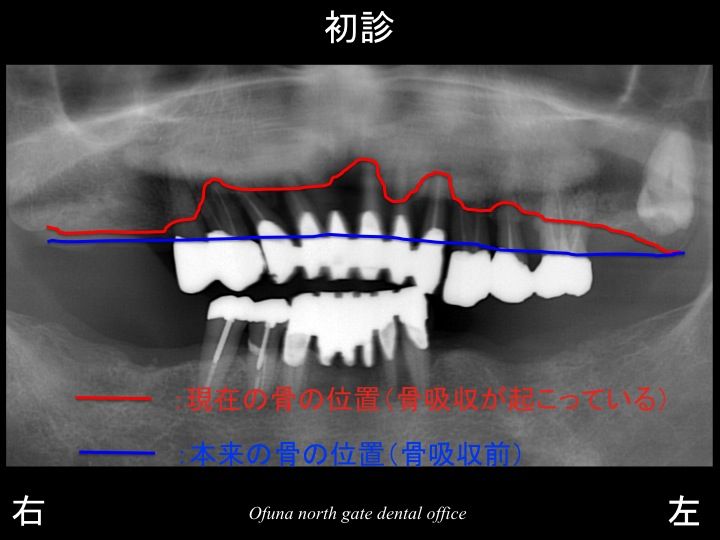

以下が初診時のレントゲンです。

上顎の前歯部の7歯分のブリッジがグラグラして噛めないとのことで来院されました。

歯周病による骨吸収 がかなりありました。

骨吸収が非常に大きかったのです。

いつものように 骨吸収の状態を分かりやすくするために

骨吸収の状態を線で書いたのが以下のレントゲンになります。

青線が骨吸収を起こす前の骨の位置です。

赤線は、現在の骨の位置です。